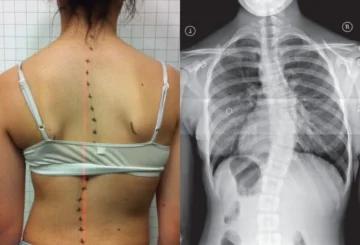

معدل التصحيح الأولي لحزام اعوجاج العمود الفقري: مفتاح التنبؤ بنجاح العلاج لدى المراهقين يعاني بعض الأطفال والمراهقين من حالة تُعرف باسم اعوجاج العمود الفقري مجهول السبب لدى المراهقين، وهي انحناء جانبي في العمود الفقري